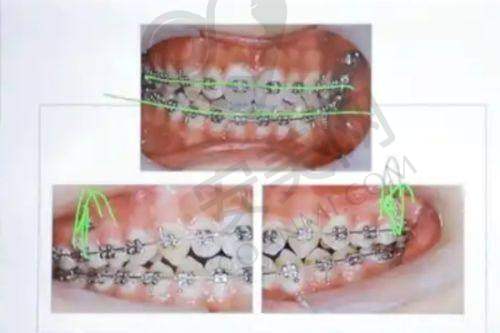

对于金属自锁托槽矫正,刘医生也有着深厚的造诣。金属自锁托槽矫正具有矫正速度快、成效稳定等特点。刘医生在操作过程中,能够精细地将托槽粘贴在牙齿上,并根据患者的牙齿情况调整弓丝的力度,以达到至佳的矫正成效。在治疗过程中,她会定期检查患者的牙齿移动情况,并及时调整矫正方案,确保矫正过程的顺利进行。